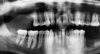

Three months later, a cone-beam computed tomography (CBCT) scan revealed the indication of a MSA due to a pneumatized right maxillary sinus with residual bone height of 2.5 mm and two Underwood septa (Figure 2). Prior to the MSA procedure, based on scientific protocols that suggest smoking cessation for at least 10 days before and after surgery,6,11 the patient was strongly advised to cease his smoking habits due to the risk of bone graft failure.

Fig 2. Preoperative CBCT scan showing a sagittal section of pneumatized right maxillary sinus in edentulous site No. 3.

Figure 2